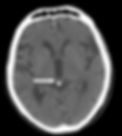

MRI Depicting Calcified Pineal